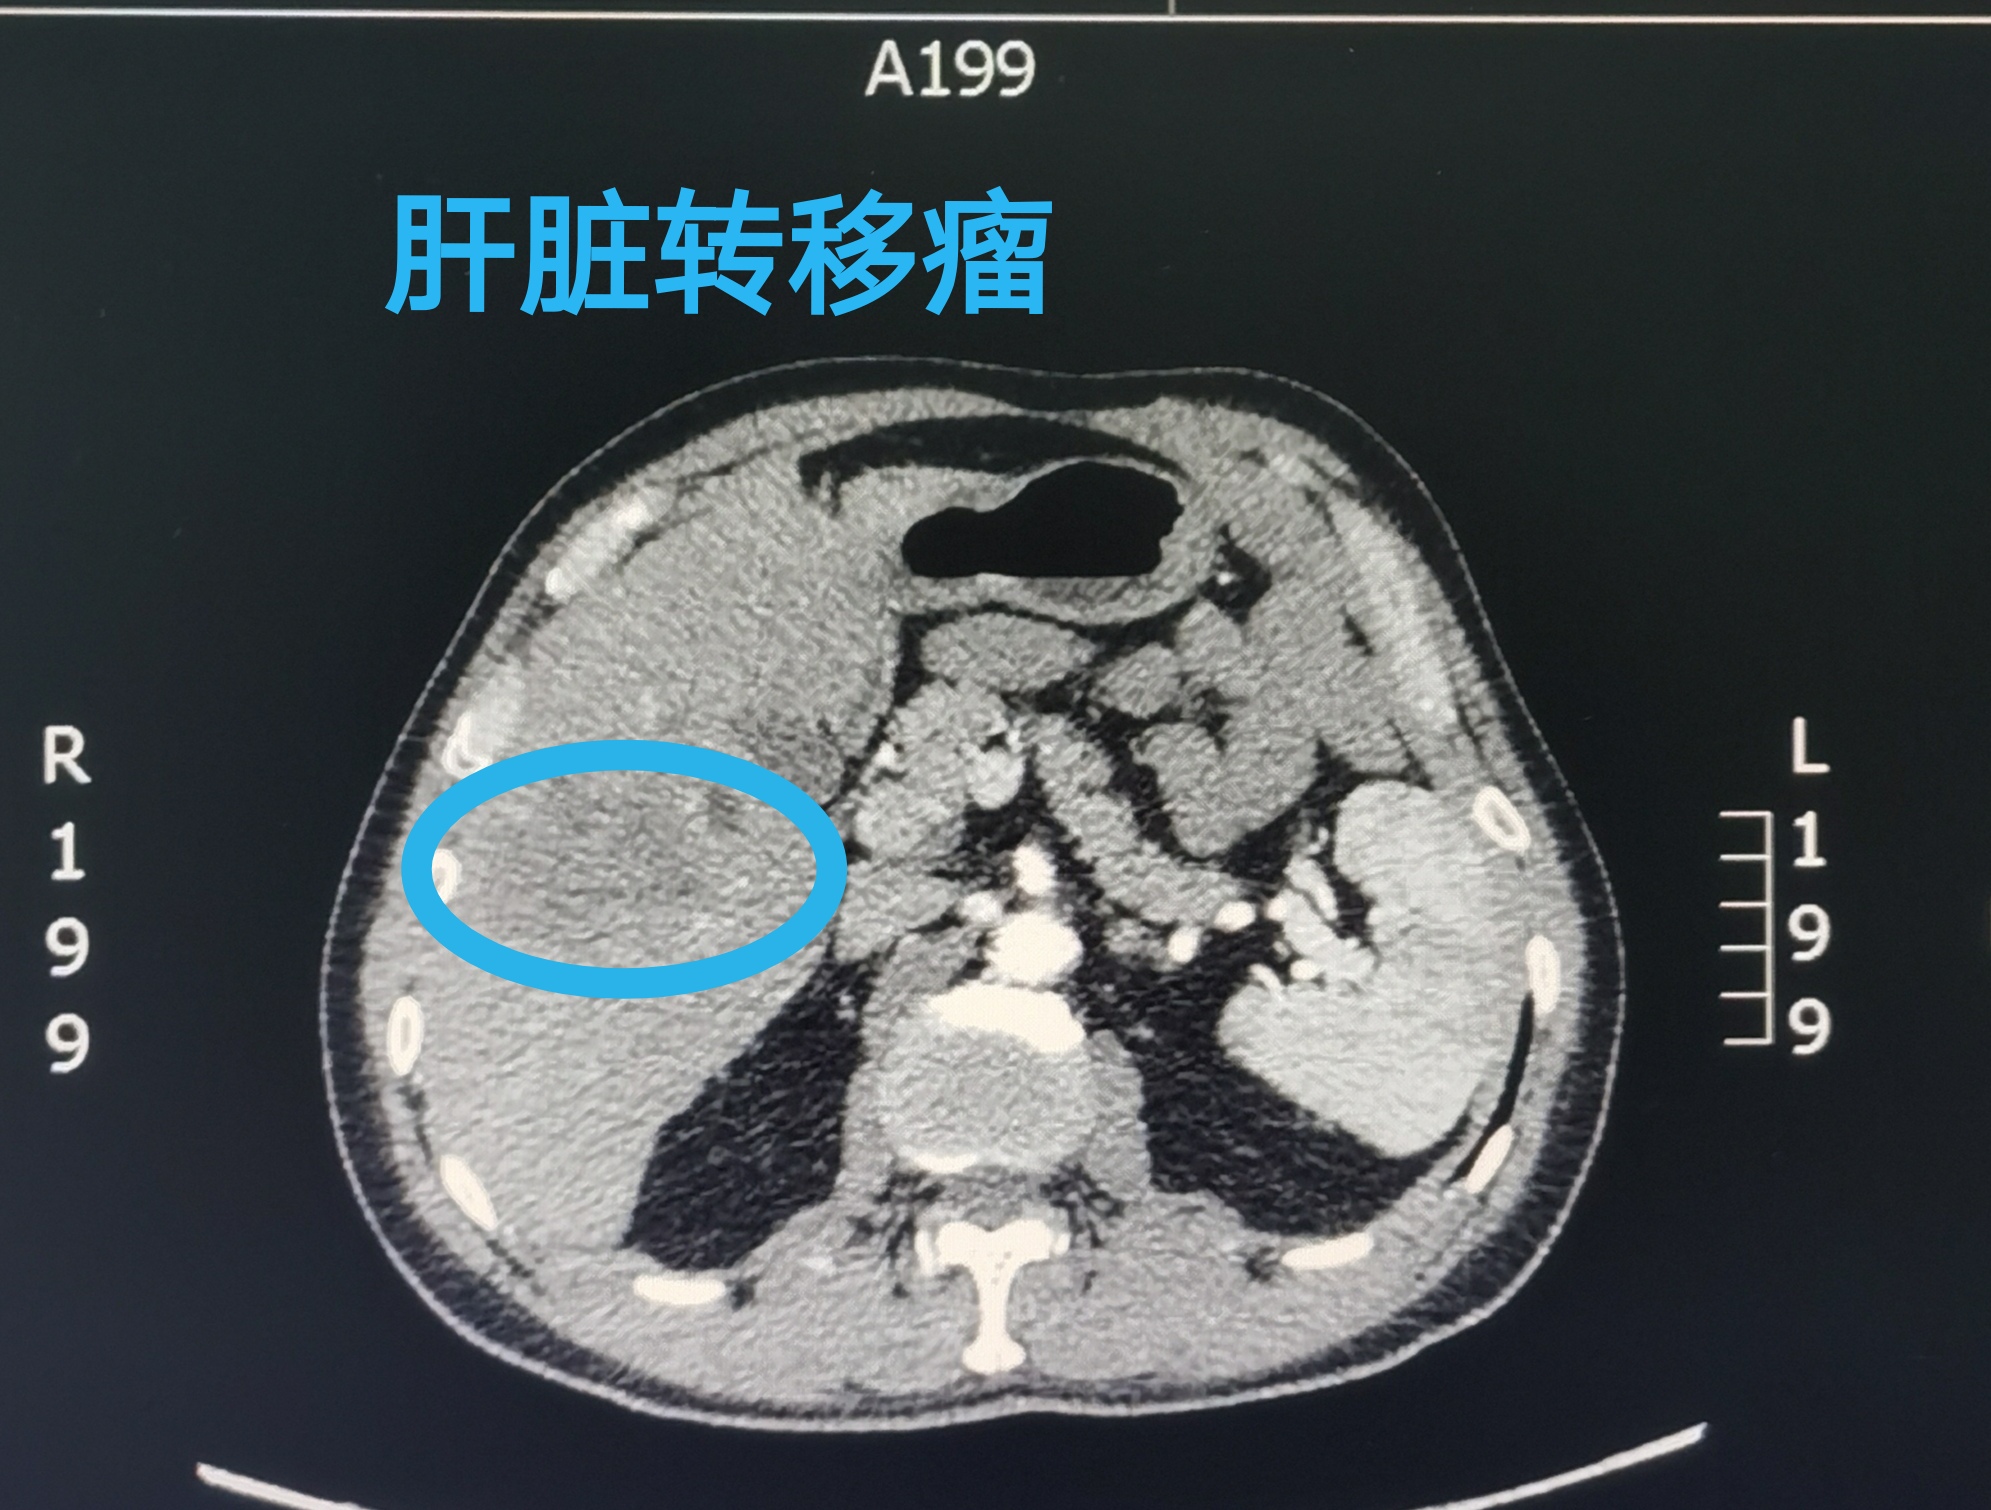

胃癌多发肝转移患者